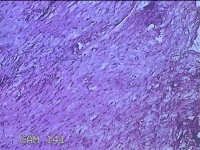

左大腿内侧包块

性别

男

年龄

21岁

临床诊断

脂肪瘤

一般病史

左大腿内侧起包块一月余。

标本名称

大体所见

灰白暗红色包块2.5x2x0.8cm一个,表面糜烂,切开包块呈实性,切面灰白暗红色,质软。

图1

图2